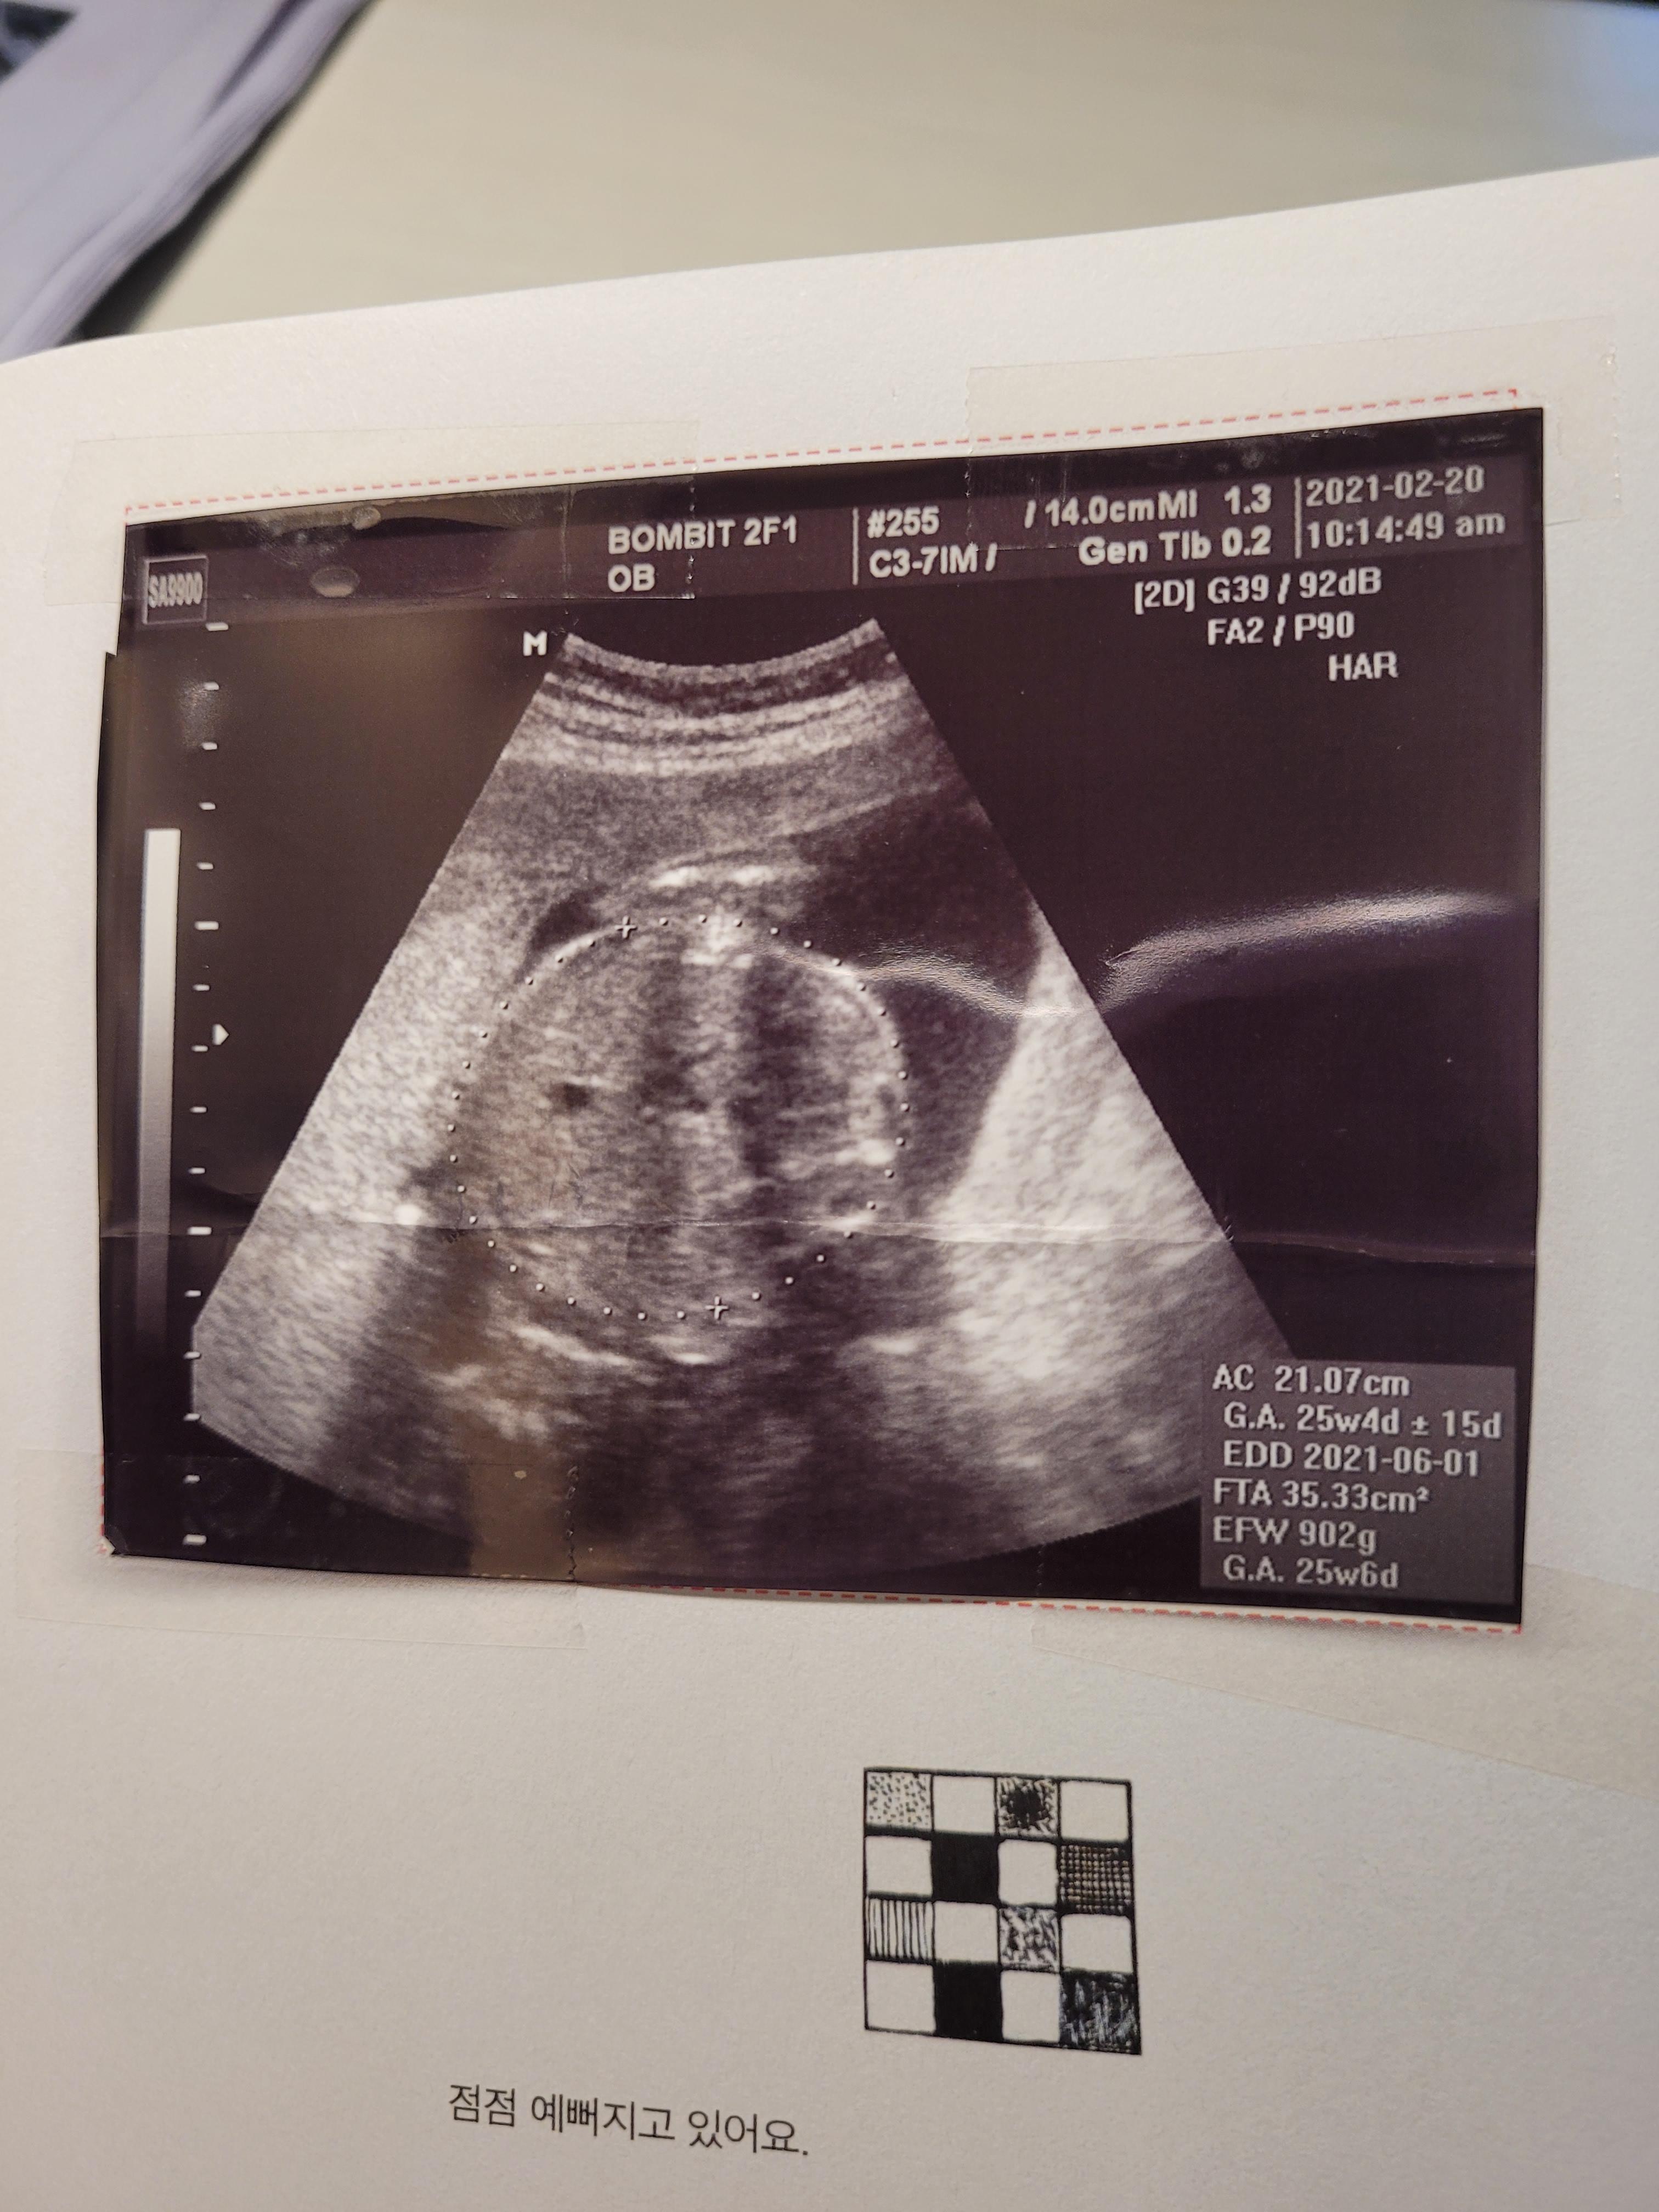

24주 초음파사진 / 24주 봄빛병원 정기검진

24주인데 2주나 앞서가는 우리 행복이..

머리둘레, 배둘레 다 체크하고 쑥쑥 잘 있는거 확인했어요.

아기는 900g정도되고, 양수도 넉넉하고 잘 있더라구요..^^